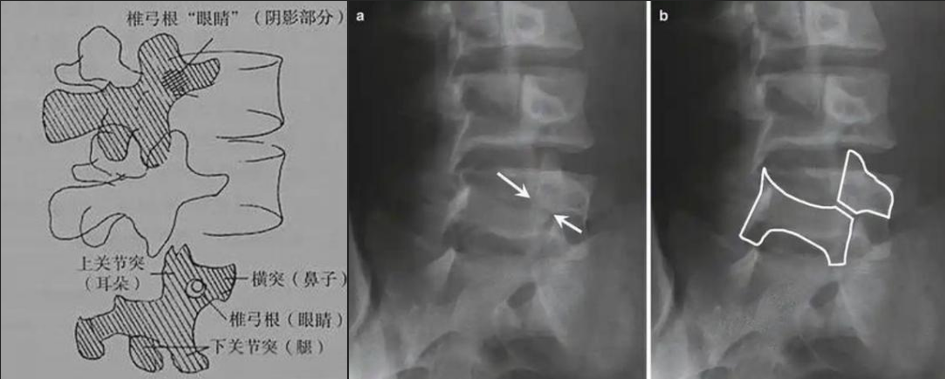

圖a和圖b 腰椎斜位:狗脖“戴項圈征”,診斷椎體椎弓峽部裂

椎弓根峽部是椎體后部椎弓上最狹窄、最薄弱、但應力最集中的部位,在常規(guī)腰椎X線正側位上,因腰椎其他結構的重疊顯示不清,但是在腰椎斜位上,能夠清楚完美地展現(xiàn)出來,若其在斜位片上表現(xiàn)為不連續(xù),則可診斷為椎弓根峽部裂,即腰椎的關鍵承重部分的骨質斷裂,這是導致青少年和運動員腰痛的主要原因。

在腰椎斜位片上,腰椎的附件結構形成了一個經(jīng)典的“斯科蒂狗”圖案,其中“狗脖子”處即代表椎弓根峽部,若“狗脖子”上出現(xiàn)了一條透亮清晰的線,就像給狗戴了一條“項鏈”,即“戴項圈征”,這是診斷椎弓峽部裂的直接證據(jù)。